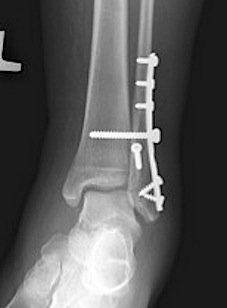

Fracture patterns

| Lateral malleolar fractures | Medial malleolar fractures | Bimalleolar fractures | Trimalleolar fractures |

Weber A - below syndesmosis Weber B - at syndesmosis Weber C - above syndesmosis |

Uncommon |

Fibular + medial malleolus Bimalleolar equivalent - fibular + deltoid ligament Fibular + posterior malleolus |

Fibular fracture + Medial malleolus fracture + Posterior malleolus fracture |